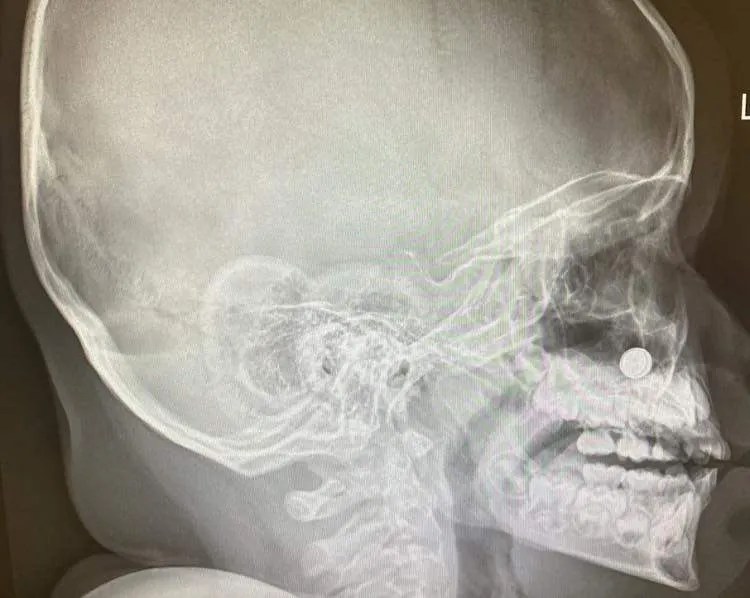

"Disc battery หรือถ่านกระดุม อันตรายมากกว่าที่คิด เพราะหากนำเข้าสู่ร่างกายแล้ว สามารถทำลายเนื้อเยื่อต่างๆในร่างกายได้จากความเป็นด่าง

เคสนี้เป็นเด็กผู้ชายอายุ 4 ปี เอานาฬิกามาเล่น แล้วถอดถ่านออกเอง ไม่รู้หนูคิดอะไรอยู่ เจ้าเด็กน้อยหยิบถ่านกระดุมใส่เข้าจมูกซ้าย เดชะบุญที่เด็กรีบบอกคุณอา ผู้ปกครองจึงรีบพามาโรงพยาบาล ป้าหมอหน้าสดกำลังจะเข้านอนก็รีบมาเข้าห้องผ่าตัดเช่นกัน เพื่อส่องกล้องเอาถ่านเจ้าปัญหาออกโดยเร็ว เพราะนี่คือภาวะฉุกเฉิน หากปล่อยไว้นานหลายชั่วโมง จะทำลายเนื้อเยื่อในโพรงจมูกน้อยๆของหนูมากขึ้นเรื่อยๆ